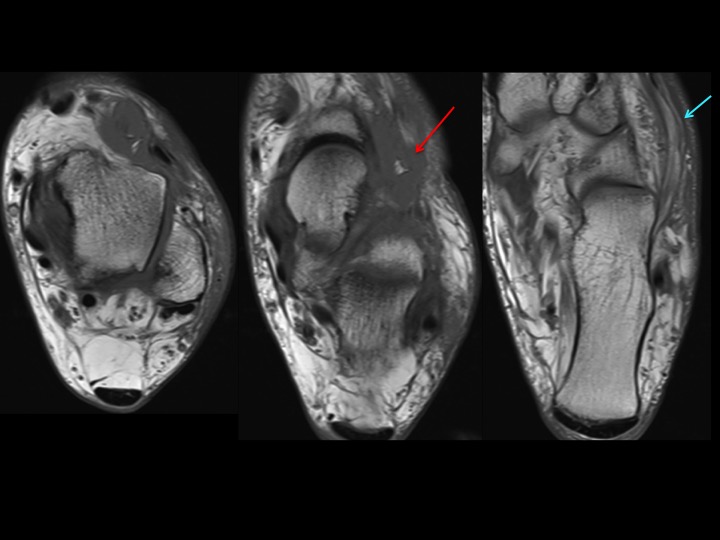

75M 4 months lateral ankle and foot pain

The Sinus Tarsi Bursa (of Gruberi) is situated between the lateral talar neck and the EDL. In this case its distended by fluid and contains thick cords of fat signal (red arrows). Would you consider this lipoma arborescens of the sinus tarsi bursa, even though the fat signal doesnt appear to branch? The majority of these bursae are soft and compressible. There is, however, atrophy and edema of the EDB muscle (blue arrow), suggesting anterior tarsal tunnel syndrome. Do you think this bursa is causing compression of the deep peroneal nerve? Reference article.